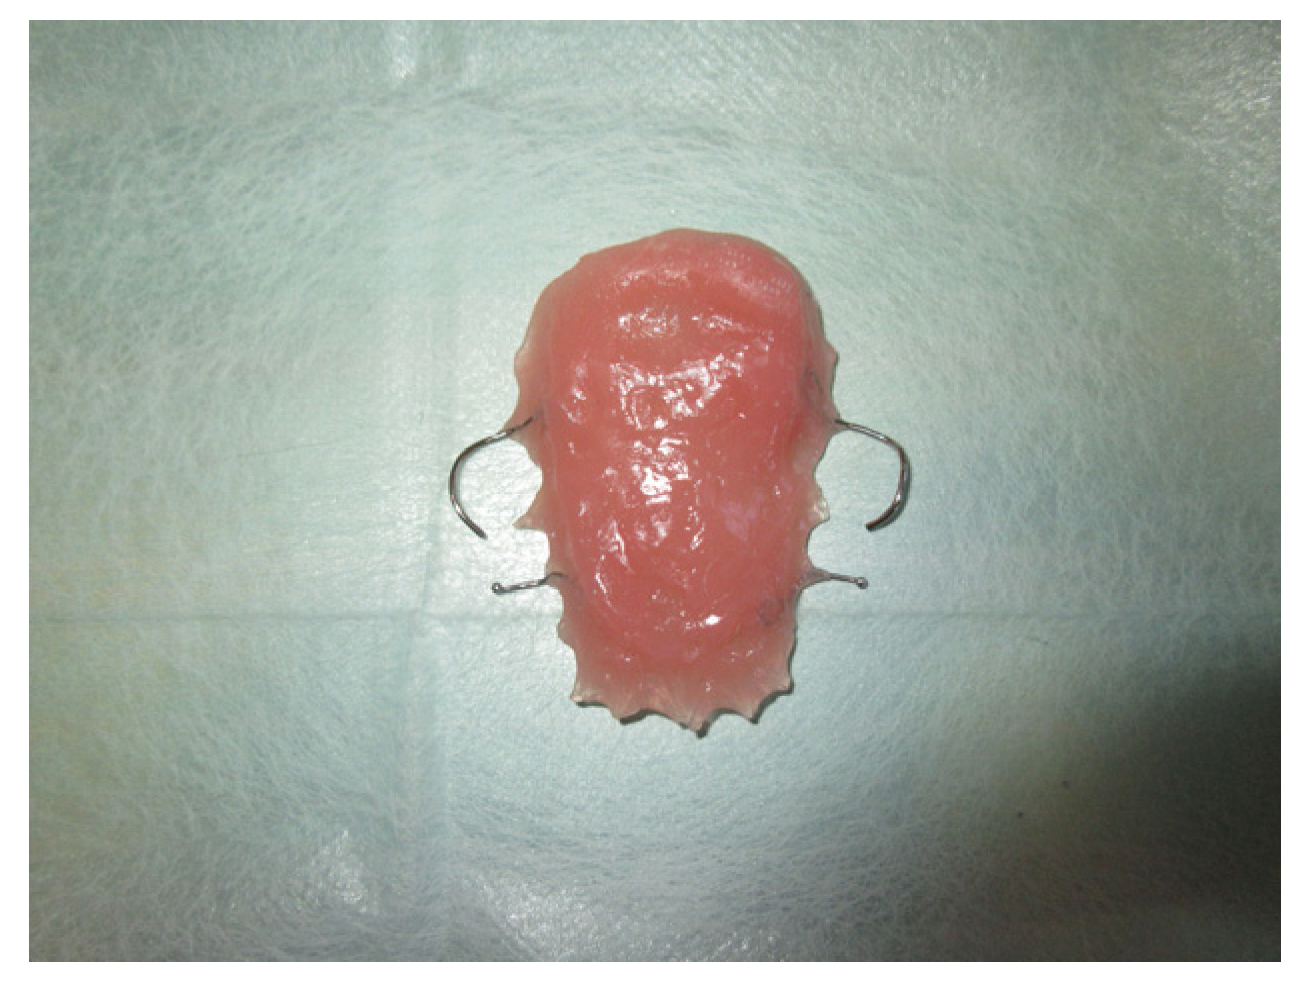

3.1.3. Case 3: R.M.

| R.M. | X | * | 9 | 0 | ||